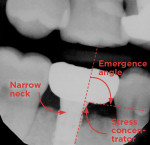

Type 2: Coronally Placed Implant, Narrow Neck

The type 2 prosthodontic profile, or "E.T." shape (Figure 3), should also prompt precautionary measures. This type of prosthesis can be the result of inadequate communication between the dental office and laboratory, or an implant placed too coronally. Historically, crown-and-bridge labs have shaped their dies on stone models with dentists aiming to keep the crown margin near the gingival border. Consequently, technicians are familiar working supracrestal down to crown margins, as this approach has been reliable for decades. When submitting an implant impression, it is essential for clinicians to include details regarding the position of the implant platform and emergence profile of a stock healing abutment. Omitting this information may lead to incorrect prosthesis construction by lab technicians that mimics what they see in the stone model only (Figure 4). The narrow neck and obtuse emergence angle can potentiate mechanical and biological complications. This seemingly innocuous mistake could lead to parts breaking, like the prosthesis, implant, and abutment, and create an alcove for pathogenic bacterial accumulation resulting in a host of negative biological consequences.8

Risks of a type 2 prosthesis can be minimized with the use of a fillet, a rounded corner that is often utilized in mechanical engineering. This approach eliminates sharp edges and improves cleansability while potentially decreasing danger. In dentistry, fillets are used to create gentler emergence profiles that reduce stress in implant solutions. Excessive tension, which is likely to accompany type 2 restorations, can cause higher levels of stress than those with fillets and should be avoided. Following this general engineering principle involving fillets should reduce the chances of complications and enable clinicians to provide safer treatment options to patients.

If a type 2 prosthesis has been designed or manufactured, the clinician can simply remake the ideal prosthesis and inform the lab to disregard the soft-tissue profile (Figure 5 and Figure 6). The clinician can then manage the soft tissue chairside and request a type 3 "heart"-shaped emergence profile. At delivery, the soft tissue can be repositioned utilizing the apical gingival displacement technique to adapt the soft tissues into an ideal functional and esthetic solution.9

To decrease risks and promote better results, prevention is vital. A simple, straightforward approach to communicating to the lab the desired emergence profile is to ask for a prosthetic outcome that resembles a type 3, or heart-shaped, design.